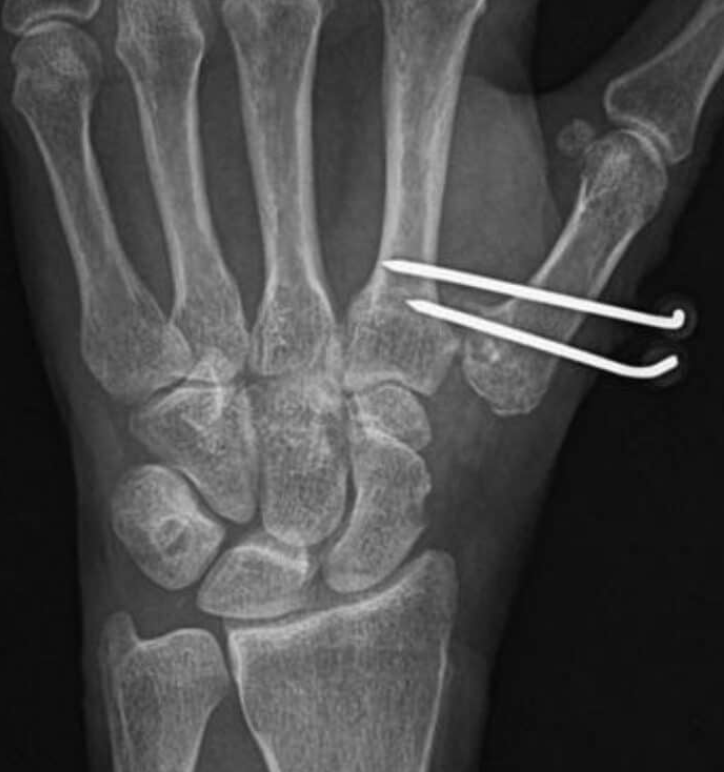

Nos estágios iniciais, procedimentos como osteotomia do primeiro metacarpo ou reconstrução ligamentar podem ser indicados, com o objetivo de melhorar a mecânica da articulação e reduzir a dor .